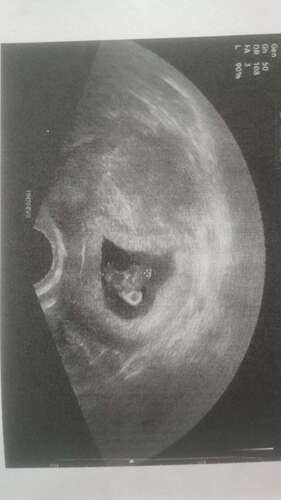

Das war 6+5 man konnte den Herzschlag schon sehen 🥹😍und hoffe nächste Woche kommt das nächste